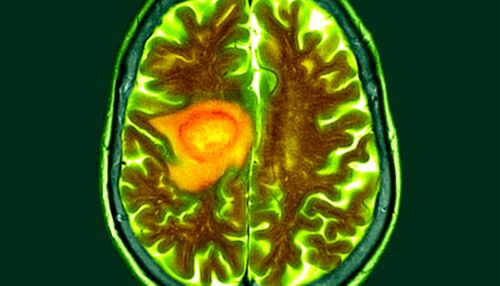

Washington University researchers have developed nano-engineered particles delivered through the nose that eliminated deadly brain tumors in mice, potentially reimagining how we approach cancers that have resisted every other treatment.